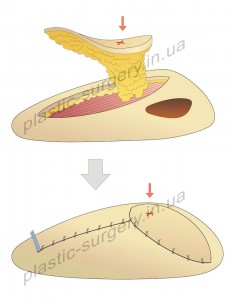

В настоящее время наиболее широко используется техника Pedicle Perforator Propeller Flap (PPPF), когда сосуд питающей ножки не скелетизируют полностью, а оставляют 1-2 см фасциальной перемычки. Это обеспечивает, с одной стороны, не сложную и безопасную ротацию данного лоскута на 180 град. и более, с хорошей адаптацией и без натяжения кожи в реципиентном ложе, а с другой – перемычка защищает сосуд от перегиба или чрезмерного растяжения. Варианты формирования лоскутов по типу питающей ножки представлены на рис.4.

Рис. 4. Варианты формирования лоскутов по типу питающей ножки: А – островковый лоскут пропеллер на подкожной питающей ножке (subcutaneous pedicle propeller flap – SPPF), с аксилярной ротацией в реципиентную зону на 90 град.; Б – островковый лоскут пропеллер на питающей ножке, состоящей из выделенных изолированных перфорантных сосудов (perforator pedicle propeller flap – PPPF) с аксилярной ротацией в реципиентную зону на 180 град.